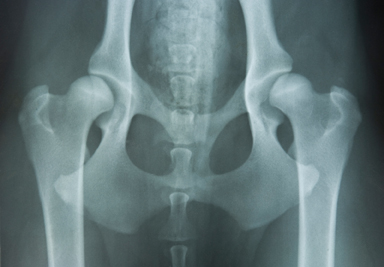

Dr. Weber is PennHip certified. This allows Dr. Weber to evaluate dogs, of any breed, for hip dysplasia using the PennHip technique. This technique measures hip distraction on a mathematical calculation rather than just subjective interpretation.

- Canine pre-breeding examination of females and males – this includes hip radiographs, general physical examination, temperament evaluation, brucellosis testing, semen evaluation, blood chemistry analysis, thyroid evaluation.